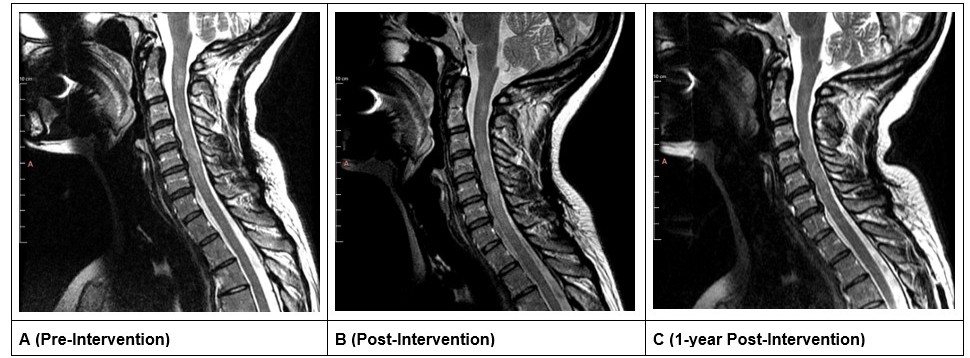

All MRI imaging obtained was assessed with Weasis DICOM Viewer (v4.6.6) and was assessed longitudinally (Figure 2) [14]. Following non-surgical spinal decompression treatment of the cervical spine, the anterior-posterior (AP) length of the lesion at C5–C6 decreased (Figures 3A and 3B) from 5.45 mm to 3.78 mm (-1.67 mm; 31% decrease) and the superior-inferior (SI) length of the lesion decreased from 10.27 mm to 9.00 mm (-1.27mm; 12% decrease; Figures 3A and 3B). After 1-year follow up, the AP length decreased by an additional 0.25 mm resulting in a total decrease of 1.92 mm (35% decrease); the SI length increased by 1.03mm at the 1-year follow-up resulting in an overall reduction of 0.24mm (10% decrease; Figures 3A and 3C).

Figure 2. Mid-sagittal slice of the cervical MRI. A is before treatment, B is after treatment, and C is 1-year follow-up.